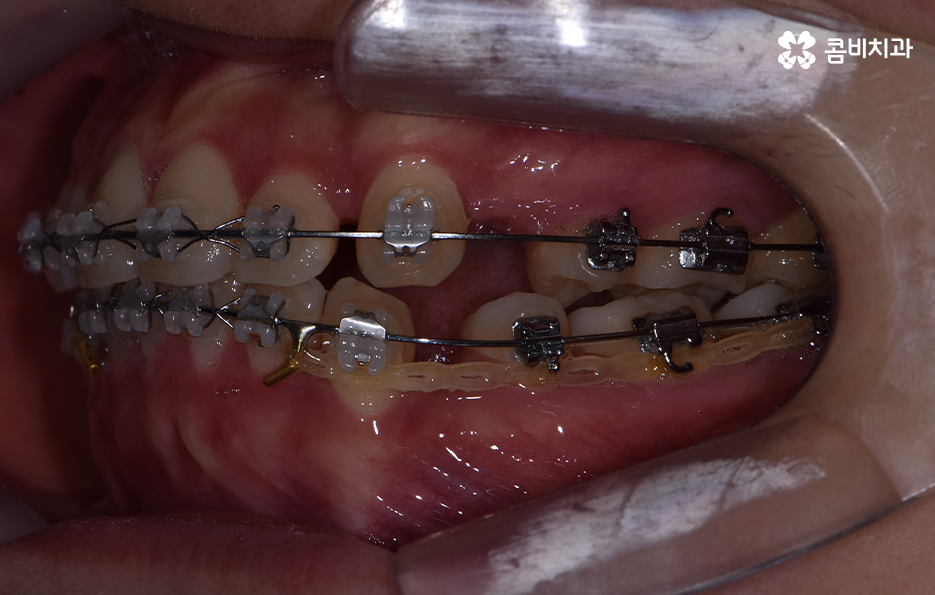

출처 아카이브 열기치아교정의 목적은 다양하지만 돌출입을 개선하고자 하는 목적성을 갖는 경우 발치가 필요한 경우가 대부분이라고 할 수 있는데요. 그 이유는 입이 나와 있는 돌출입을 개선하기 위해서는 앞니 부분이 뒤 쪽으로 들어가야 돌출입이 개선되기 때문인데 치아를 안쪽으로 이동시키기 위한 공간 확보를 위해 발치가 필요한 경우가 많은 거예요.

돌출입을 개선하기 위한 교정 치료의 사례에도 돌출입발치교정 사례가 많은 이유도 치아의 발치를 통해 앞니를 후방 이동시키는 치아 교정의 원리가 있기 때문이라고 설명할 수 있어요

오늘은 돌출입발치교정 통해서 치열도 가지런하게 교정하고 얼굴형의 변화뿐 아니라 교합까지 잘 맞물려서 건강하게 치아교정을 하는 방법에 대해 알아볼 거예요